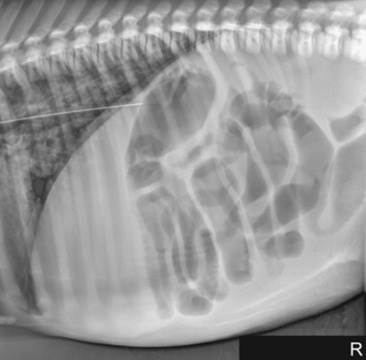

Abdominal radiography is useful to evaluate the small and large intestines for sand accumulation, enterolithiasis, impactions, or small intestinal disorders in foals. When sand is ingested, it generally will accumulate within the large colon along the ventral abdomen8 (Fig. 32-4). Radiography has been found to be a useful method to monitor the resolution of sand impactions after medical management; however, sequential examinations are needed to verify that the volume of sand has reduced.8 If the volume of sand is large enough, it is difficult to determine if an enterolith is present because of summation of the two lesions. Enteroliths are a solid concretion of mineral that usually forms around a nidus, such as a metallic foreign body (Fig. 32-5). The mineral composition is varied, as illustrated by the different opacities present within the enterolith. Radiographs have a 96.4% positive predictive value to detect enteroliths in high-prevalence areas. These enteroliths were generally found to be within the midabdominal radiograph, and 67% of small colon enteroliths caused large colon distention, which was also identified on radiographs.7 Impactions are more difficult to diagnose because usually there is just increased feed accumulation within the abdomen. Although no enterolith or obstruction is identified, granular material can be seen, usually within the ventral colon near the sternal flexure. This is because pelvic flexure impactions will cause the feed material to accumulate orad, causing distention of the left ventral colon (Fig. 32-6). Intestinal disorders such as functional ileus secondary to enteritis (Fig. 32-7) or obstruction secondary to intussusception or meconium impaction (Fig. 32-8) in foals can also be identified on abdominal radiographs. These images show large dilation of the small intestine, and differentiation between functional and mechanical ileus in foals is generally based on the size of the intestine and the volume of gas that is present.9 Evaluation of the abdomen using ultrasound may aid in qualifying the small or large intestinal motility as well as identifying the source of an obstruction if the determination on radiographs cannot be made.

image

Fig. 32-7 Standing lateral radiograph of a 1-day-old, premature quarter horse filly. Note the large amount of gas-distended intestine. Because of the large amount of small intestinal distention, functional ileus is the primary differential diagnosis.

Fig. 32-8 Standing lateral radiograph of a 2-day-old thoroughbred colt with a meconium impaction. Note the large amount of gas distention of the colon.